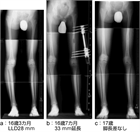

1. 小学校就学前に3㎝程度の脚長差が発生する可能性が高い患児は創外固定器による脚延長を行い、延長側を1㎝程度余分に行い就学前に治療を終了する。その後脚長差が再発した場合は第2次成長期に8 plateによる成長抑制術を行うように計画することが最も負担が少ない治療法である。